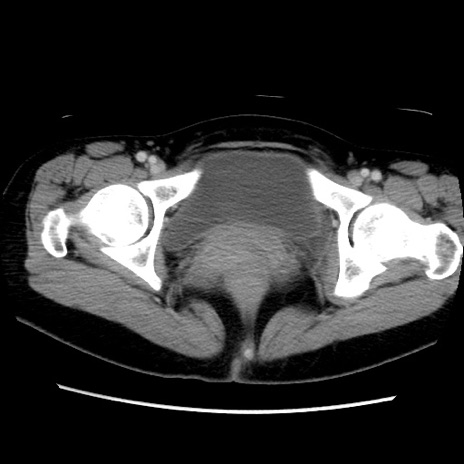

MRI(4日後)

【症例】40歳代女性

【主訴】上下腹部痛

【現病歴】2日目から下腹部痛あり。夜間は痛みで眠れなかった。昨日より上腹部痛と下痢が出現。臥位で痛みは軽快したため、休んでいた。本日になって臥位でも立位でも痛みが強くなってきたため救急要請。

【既往歴】子宮内膜症

【身体所見】部:平坦・軟、左上下腹部に圧痛あり、反跳痛あり。

【データ】WBC 21800、CRP 26.78